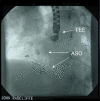

Atrial septal defect closure is now routinely performed using a percutaneous approach under echocardiographic guidance. Centrally located, secundum defects are ideal for device closure but there is considerable morphological variation in size and location of the defects. A small proportion of atrial septal defects may have multiple fenestrations and these are often considered unsuitable for device closure. We report three cases of multiple atrial septal defects successfully closed with two Amplatzer septal occluders.